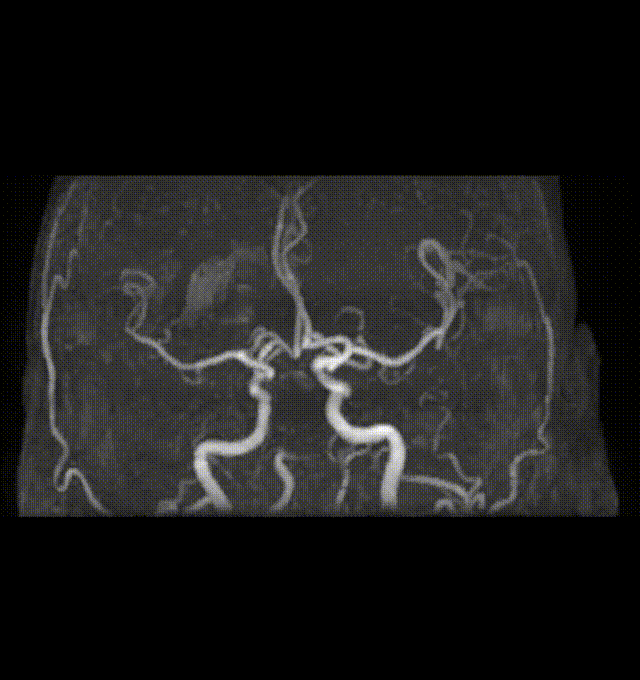

患者突发意识模糊,四肢僵硬,急诊MR DWI+MRA提示基底动脉闭塞,右椎主供血。

术前DWI +MRA

结合病史,患者基底动脉闭塞考虑为房颤栓子脱落导致,患者腹主动脉、双髂总动脉、双髂外动脉、双侧髂内动脉完全闭塞。

只能考虑经桡动脉取栓,拟定经右桡动脉-右椎动脉取栓治疗。